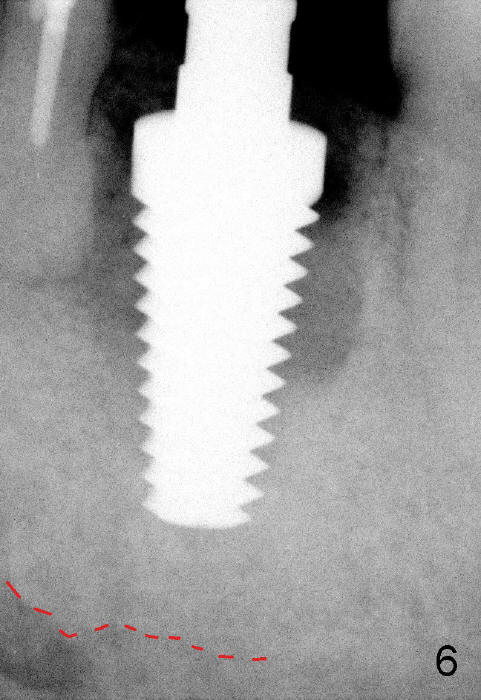

When a 7x17mm tap is inserted, it is stable. There is distance to the inferior alveolar nerve (Fig.6: dashed line).